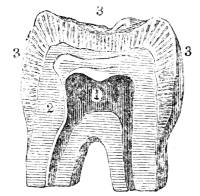

by minute vesicles of an oblong form. The termination

of the bronchi in the human lung presents

a strikingly analogous appearance. Malpighi, who

with extraordinary talent and success devoted his

life to the investigation of the minute structures of

the various organs of the human body, represents

the mucous membrane of the bronchial tubes as

terminating in minute vesicles of unequal size: and

Reisseissen, who has more recently resumed the

inquiry and examined this structure with extreme

care, agrees with Malpighi in stating that the

bronchial tubes at their terminal points expand

into minute, delicate, membranous vesicles of a

cylindrical and somewhat rounded figure (fig.

CXXXVIII. 2). The bronchial tubes do not divide

to any great degree of minuteness (fig. CXXXVIII.

1), but terminate somewhat abruptly in the vesicles46

(fig. CXXXVIII. 2), which though minute are large

enough to be visible to the naked eye (fig.

CXXXVIII. 2). Viewed in connexion with the

bronchial tubes at their terminal points, the vesicles

present a clustered appearance, not unlike

clusters of currants attached to their stem (fig.

CXXXVIII. 2).